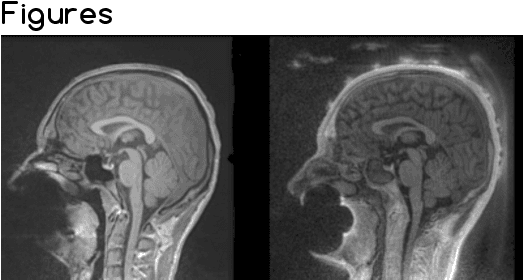

Abstract:Simultaneous EEG/fMRI acquisition allows to measure brain activity at high spatial-temporal resolution. The localisation of EEG sources depends on several parameters including the position of the electrodes on the scalp. The position of the MR electrodes during its acquisitions is obtained with the use of the UTE sequence allowing their visualisation. The retrieval of the electrodes consists in obtaining the volume where the electrodes are located by applying a sphere detection algorithm. We detect around 90% of electrodes for each subject, and our UTE-based electrode detection showed an average position error of 3.7mm for all subjects.